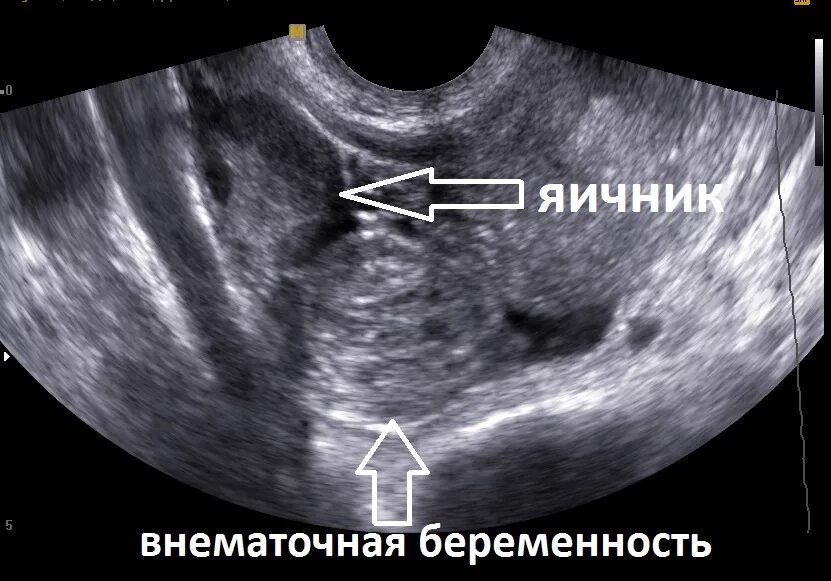

Можно ли увидеть внематочную беременность